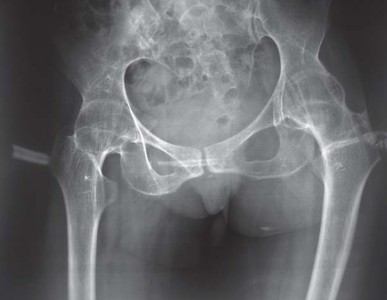

لوحظت ثلاثة أنماط مميزة لإصابة الورك لدى مرضى التهاب المفاصل الروماتويدي اليفعي:

* الإصابة المبكرة (قبل سن 11 عامًا): يعاني المرضى من وركين مشوهين (خلعيين) مع رؤوس فخذ كبيرة ومتقوسة وتجويف حقي مشوه.

* الإصابة المتأخرة: غالبًا ما تظهر على المرضى حالات انغماس حقي شديد (بروز الحُق).

* التهاب المفاصل المرتبط بالتهاب المرتكزات: يظهر هؤلاء المرضى بتكلس عظمي لمفصل الورك.